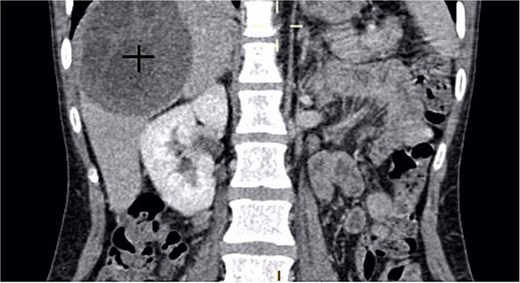

A 30-year-old woman, gravida 2 para 2, presented with a 10-day history of right upper quadrant (RUQ) abdominal pain. She had no significant medical or surgical history and denied systemic symptoms such as fever, weight loss, or fatigue. On examination, she was afebrile and hemodynamically stable, with a WHO performance status of 1. Abdominal palpation revealed localized tenderness in the RUQ. Laboratory investigations revealed mild leukocytosis (12 250/μL), Hb:10.8 g/dL, Plt:538000, TP:64%, Na:132 mmol/L, K:4.1 mmol/L, CRP:299 mg/L. Liver function tests showed GGT:36 U/L, PAL:46 U/L, ASAT:13 U/L, ALAT:6 U/L, total bilirubin:5 mg/L, direct bilirubin:3 mg/L. Urea and creatinine were 0.2 and 3.6, respectively. Contrast-enhanced CT revealed a large mass in the gallbladder bed, suspected to be a tubulo-papillary intracholecystic neoplasm (ICPN) (Figs 1 and 2), with an associated angiomatous liver lesion in segment III, hydatid cysts, and mild ascites. Exploratory laparotomy was performed, revealing a ruptured gallbladder tumor with extension into adjacent liver tissue and abdominal wall, and free biliary stones within the peritoneal cavity (Fig. 3).

Axial CT scan revealing a gallbladder tumor with invasion of adjacent structures.